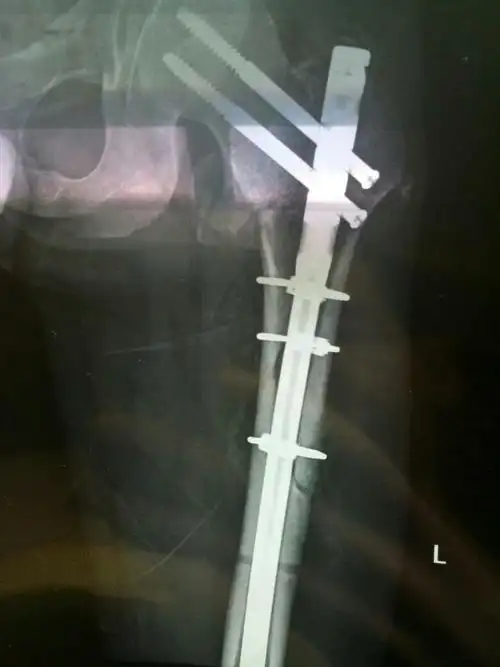

陈旧性pilon骨折病例的手术治疗

三亚市中医院骨一科之警示篇:股骨干合并颈骨折

股骨干合并股骨颈骨折的治疗.

双侧股骨干骨折术后